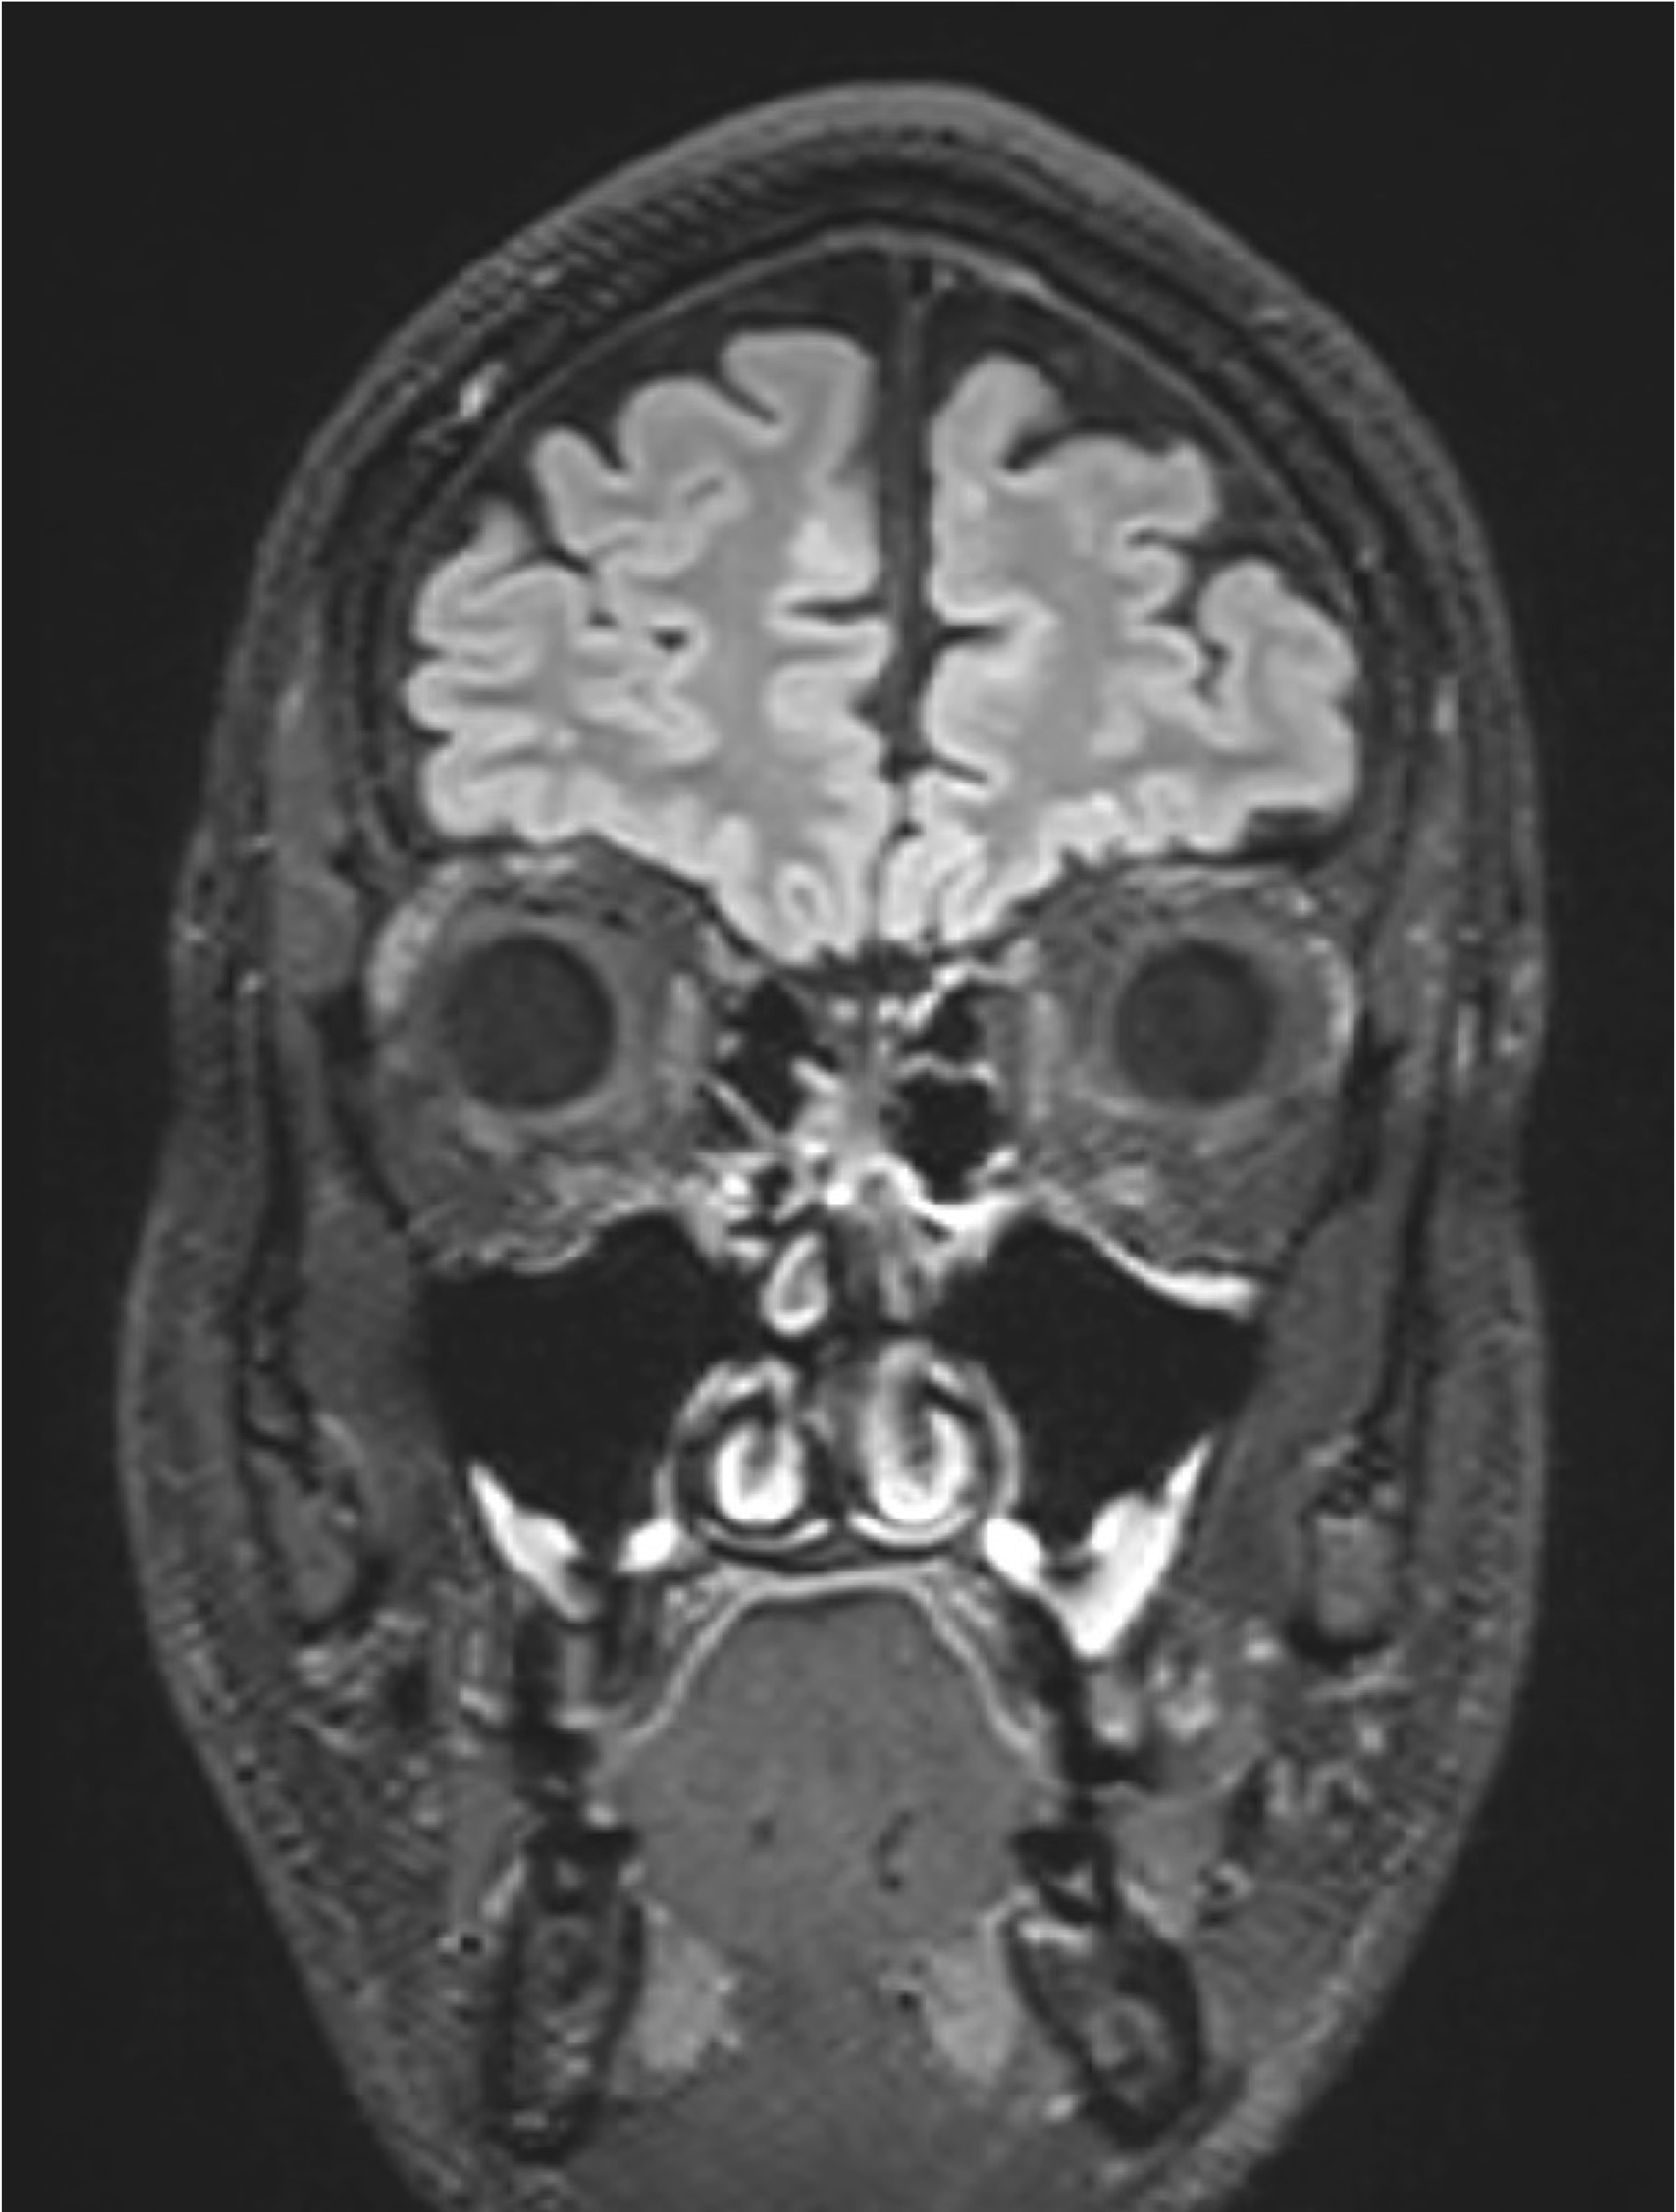

BU: Die Aufnahmen aus der Magnetresonanztomographie zeigen einen jungen Patienten mit Multipler Sklerose mit mehreren entzündlichen Läsionen des Gehirns. (© Radiologie Innsbruck)

Abseits klinischer Symptome, die von Einschränkungen des Sehvermögens bis hin zu Lähmungserscheinungen ein breites Spektrum umfassen, kann die Krankheitsaktivität bei MS auch bildgebend dargestellt werden. „Der Nachweis entzündlicher Läsionen im Gehirn mittels MRTerlaubt auch eine Einschätzung geringerer Krankheitsaktivität, denn vermeintlich stabile Patient:innen können trotz Therapie weiterhin neue, klinisch stumme, entzündliche Veränderungen entwickeln“, weiß Neuroimmunologe Harald Hegen, der an der Innsbrucker Univ.-Klinik für Neurologie bereits seit vielen Jahren zu MS forscht.

In die Studienkohorte wurden 131 MS-Patient:innen aus MS-Zentren in Österreich und der Schweiz eingeschlossen, die unter einer gering- bis moderat-effektiven Immuntherapie zwölf Monate lang klinisch stabil waren und dann einer MRT unterzogen wurden. „Wir konnten zeigen, dass Patient:innen mit schubförmiger MS, die unter Immuntherapie zwei oder mehr neue entzündliche MRT-Läsionen innerhalb eines Jahres entwickeln, auch bei klinischer Stabilität, also ohne Symptome, von einem Wechsel auf eine hoch-effektive Immuntherapie profitieren“, beschreibt Erstautor Gabriel Bsteh von der Medizinischen Universität Wien die zentrale Erkenntnis. Damit liefert die Studie eine für den klinischen Alltag wichtige Erkenntnis, die für die individuelle Therapieanpassung genutzt werden sollte.

„Nachdem Läsionen oft schon vor dem Auftreten klinischer Symptome in der MRT sichtbar sind, ermöglicht eine bildgebende Kontrolle bei Patient:innen mit einer gering- bis moderat-effektiven Therapie ein frühes Eingreifen in den individuellen Krankheitsverlauf“, betont Studienleiter Harald Hegen. In der Studienkohorte waren rund 40 Prozent der Patient:innen klinisch stabil, zeigten allerdings in der MRT schon eine oder mehrere Läsionen. Bislang war in der klinischen Praxis eine Therapieverstärkung nur nach Auftreten klinisch manifester Symptome angezeigt.